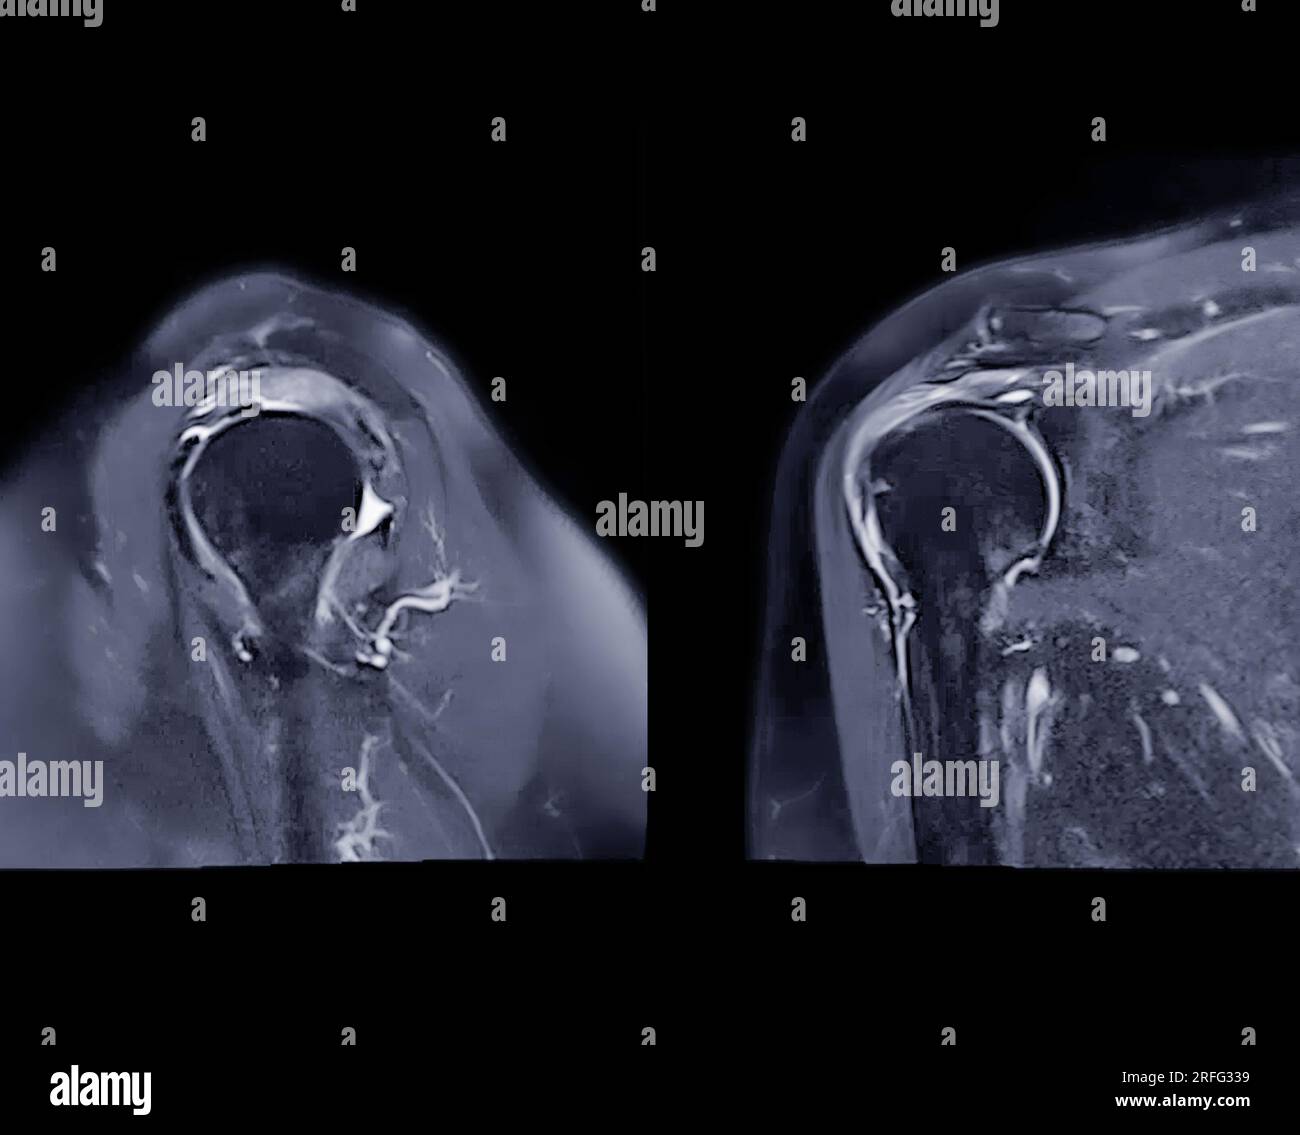

Resonance Imaging or MRI of Shoulder Joint Sagittal and Coronal Shoulder Mri Setup This mri shoulder coronal cross sectional anatomy tool is absolutely free to use. Mri of the shoulder is typically performed in three orthogonal planes—axial, coronal, and sagittal—with respect to the. Indirect mr arthrography of the shoulder: Use the mouse scroll wheel to move the images up and. The glenohumeral joint is a synovial joint, formed by the glenoid fossa of. Coronal Shoulder Mri Setup.

MRI Shoulder Joint Axial, Coronal and Sagittal Plane Stock Photo Coronal Shoulder Mri Setup ⮚ presence of a joint effusion ⮚. Use the mouse scroll wheel to move the images up and. Position the patient in supine position with head pointing towards the magnet (head first supine) position the. The glenohumeral joint is a synovial joint, formed by the glenoid fossa of the scapula and the head of the humerus, while the. The shoulder. Coronal Shoulder Mri Setup.